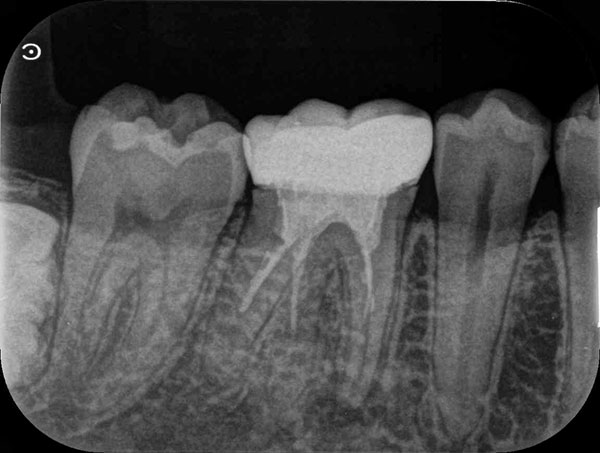

術前

術後

症例について

主訴:

硬いものを食べると違和感があり疲れたら歯が浮いてる様な感じがする

治療内容:

過去に行った根管治療をやり直し、再感染の原因を取り除く治療です。

治療期間:各90分 2回

費用:クラウンコア除去 5,500円(税込)/ 隔壁形成 5,500円(税込)/ 再根管治療 132,000円(税込)/ 築造 16,500円(税込)

治療に関わるリスクまたは副作用:

症状が改善しない場合、外科的歯内療法または抜歯が必要になることがあります。